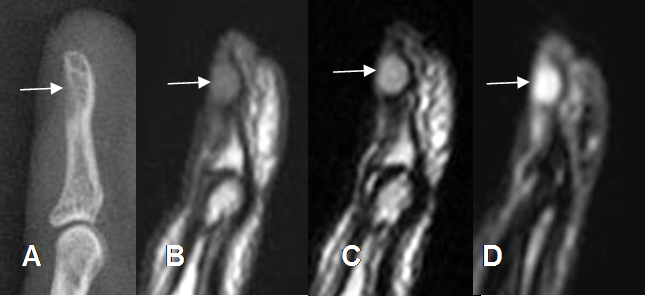

Fig 217 C. Quiste de inclusión.

A: Rx lateral, B: RM sagital en T1, C: RM sagital en T2 y D: RM sagital en STIR.

Lesión de tejidos blandos y consistencia quística, que erosiona la parte posterior de la falange distal, del 3º dedo.